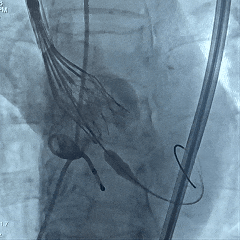

25号瓣膜释放至全展开

造影评估:瓣膜位置可,形态稳定

多角度评估,瓣膜位置可

脱钩后造影,瓣膜位置可,几乎无瓣周漏